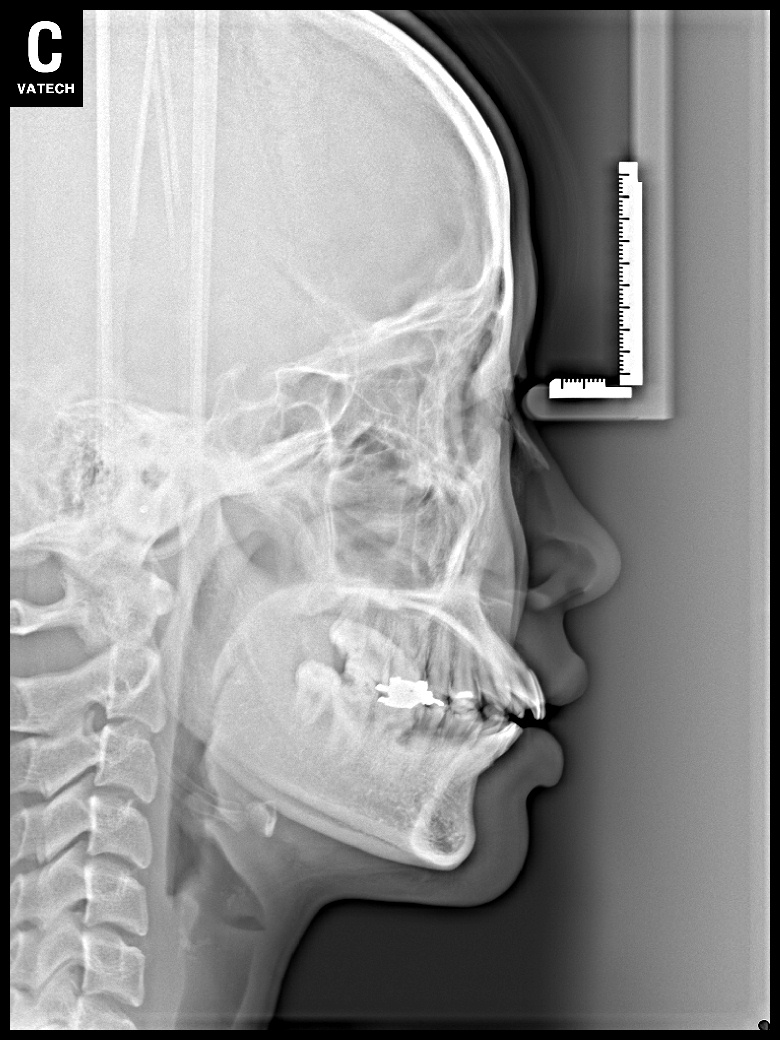

치료 전 사진입니다.